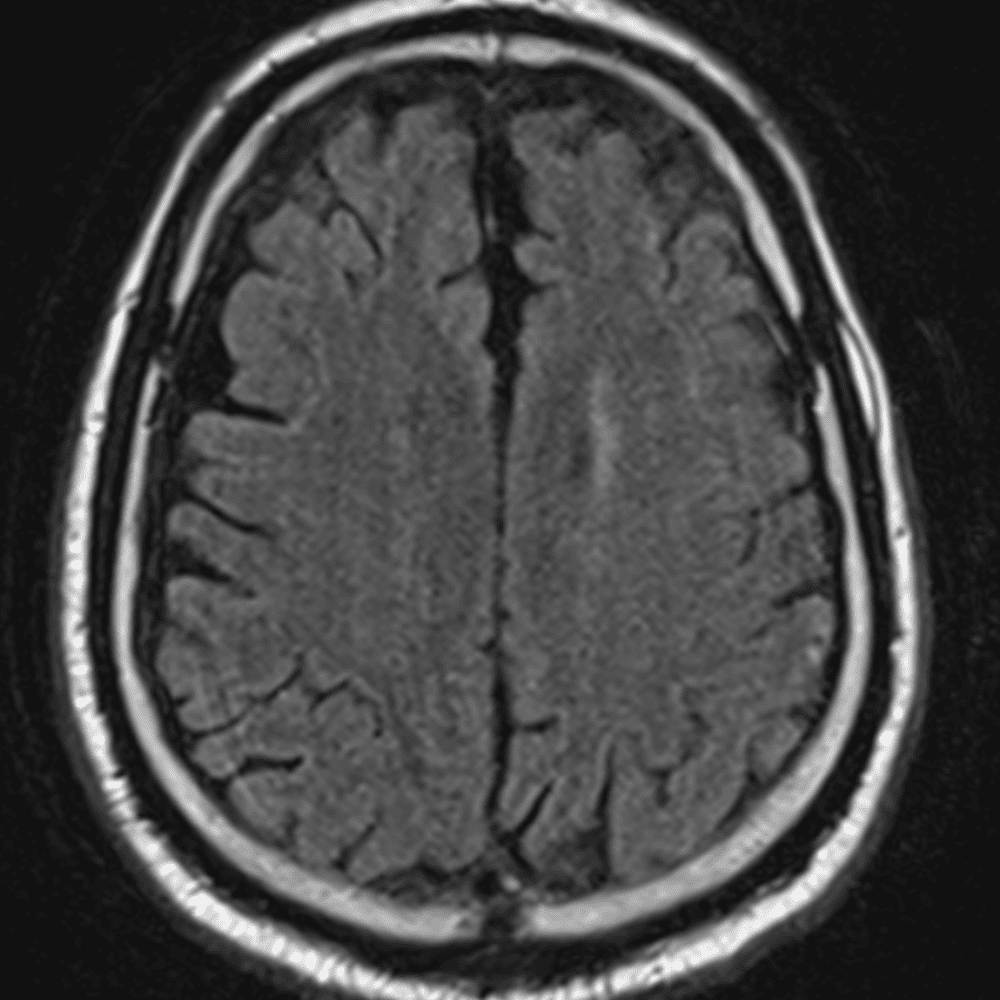

์—ฐ์Šต

๋ฏธ๋ฌ˜ํ•˜๊ฑฐ๋‚˜ ์–ด๋ ค์šด ์‚ฌ๋ก€์™€ ์ผ๋ถ€ ์ •์ƒ ์‚ฌ๋ก€๋ฅผ ํฌํ•จํ•˜์—ฌ ๋‹น์ง์„ ์‹œ๋ฎฌ๋ ˆ์ด์…˜ํ•ฉ๋‹ˆ๋‹ค.

50 ์‚ฌ๋ก€